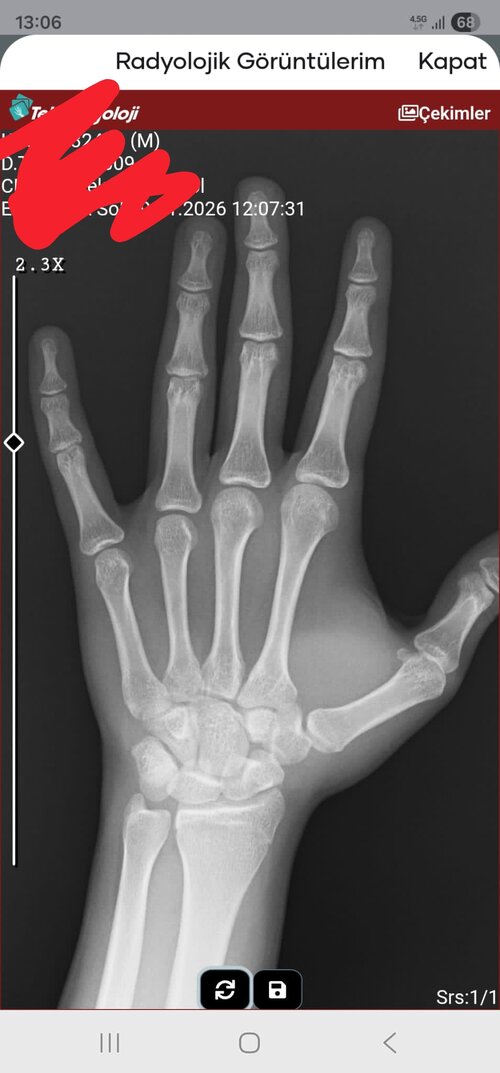

IMG 20260129 134828 açık mi yoksa değil mi?